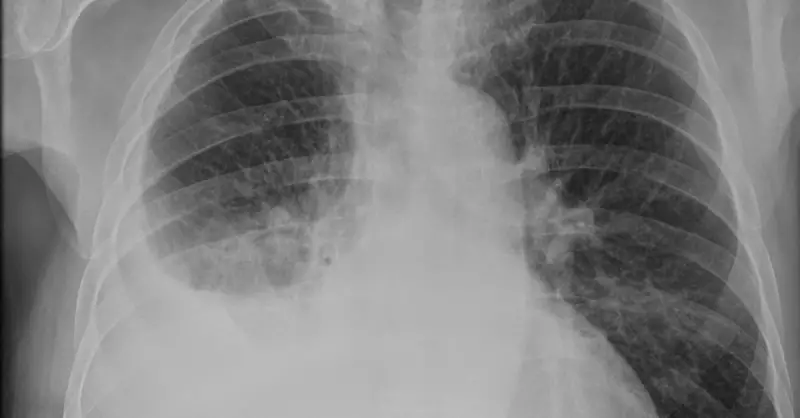

Tıp dilinde plevral efüzyon olarak adlandırılan akciğerde su toplanması, akciğer zarları arasında sıvı birikmesi sonucu ortaya çıkan ciddi bir sağlık sorunudur. Bu durum, nefes darlığı ve göğüs ağrısı gibi belirtilerle kendini göstererek hastaların yaşam kalitesini önemli ölçüde etkileyebilir.

Hastalığın teşhisinde göğüs röntgeni, bilgisayarlı tomografi ve ultrasonografi gibi görüntüleme yöntemleri kullanılır. Gerektiğinde, torasentez işlemiyle sıvı örneği alınarak laboratuvar analizi yapılır.